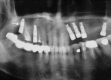

Purpose: To report the clinical and radiological characteristics of a patient who experienced dental implant displacement into the maxillary sinus following sinus floor elevation, and to compare our findings with those of other published reports of the displacement of dental implants.

Materials and methods: Implant placement and maxillary sinus elevation were performed simultaneously. The location of the displaced implant was monitored for 8 years, until the ectopic implant was surgically removed using the lateral window approach. The contributing factors, treatment modality, and clinical outcome for our patient were compared with those of patients reported in the literature.